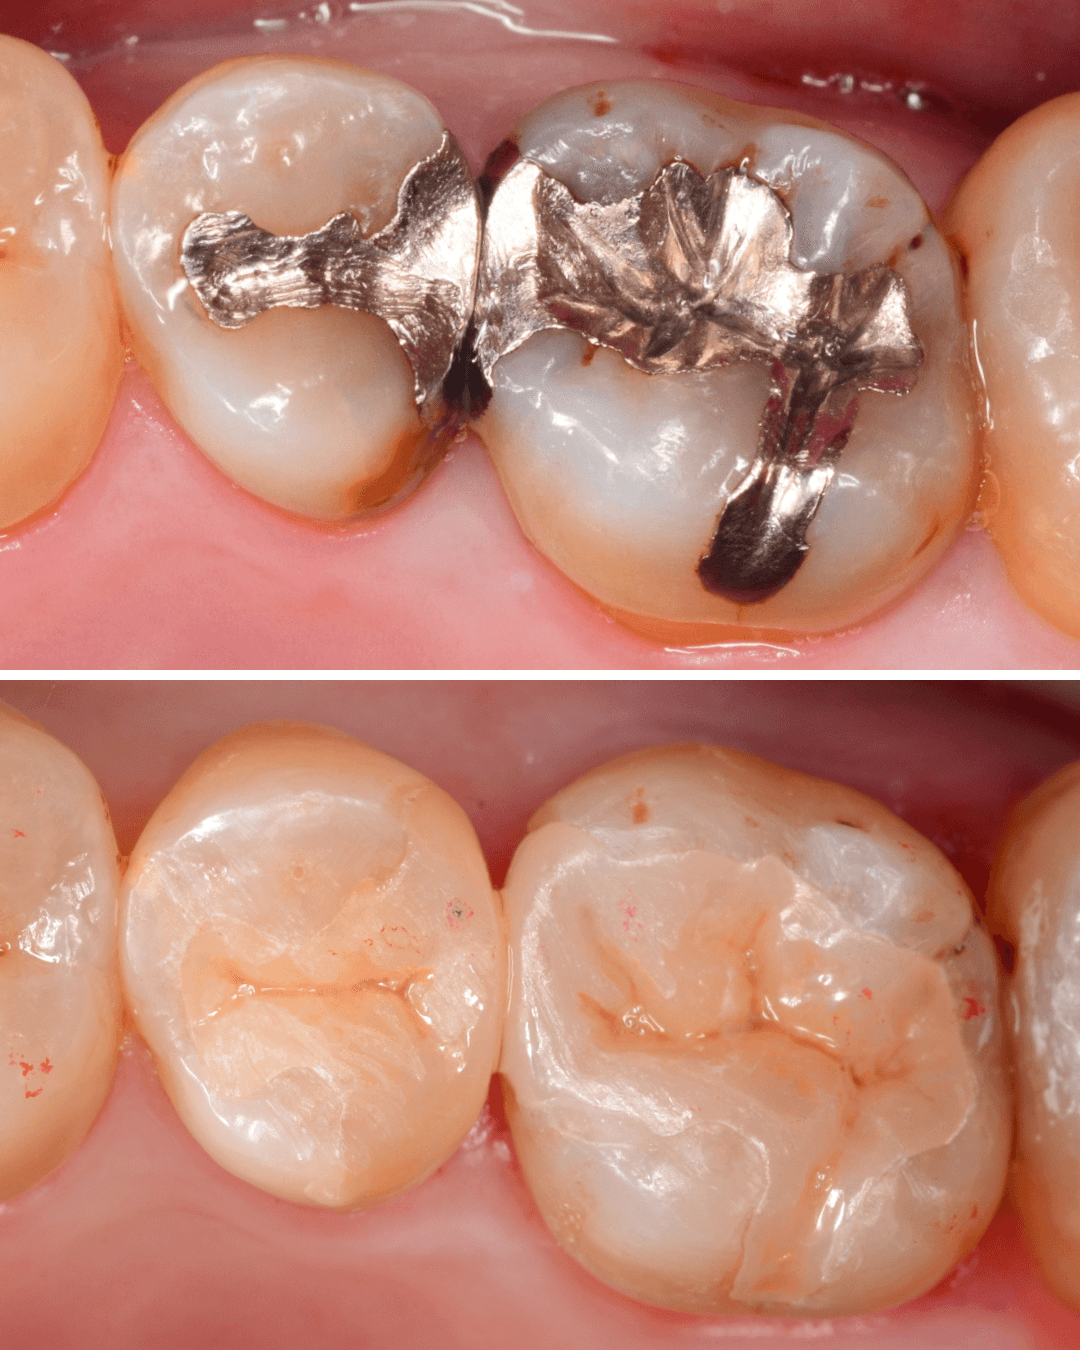

Case.20 メタル・インレーとメタル・クラウンをジルコニアにやり替え

「下の奥歯の銀歯を白くしたい」というご希望の患者さんです。

メタル・インレーとメタル・クラウンが入っていますね。

set後の写真です。

患者さんにも満足していただける仕上がりになりました。

治療前後の写真になります。

やはり、印象が大きく変わりますね。